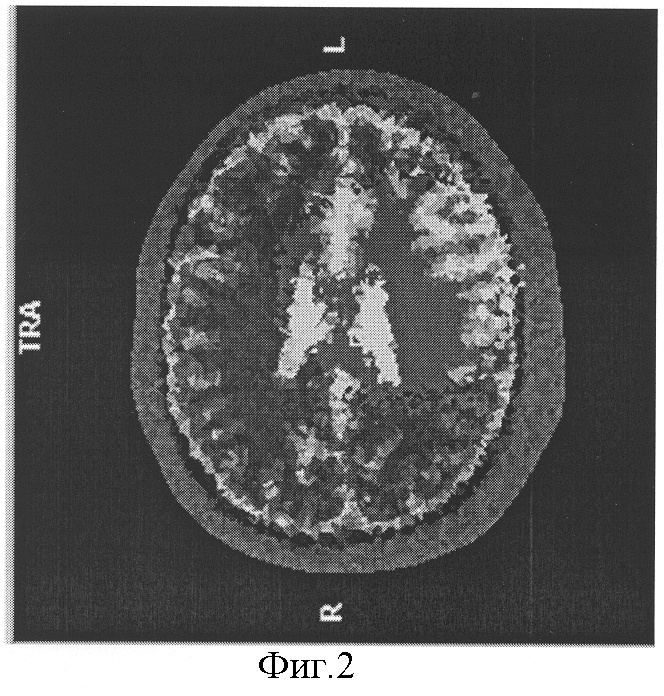

На фиг.2 изображен очаг нарушения перфузии головного мозга по данным электроэмпедансной томографии в правой теменной доли.

Диагноз был подтвержден ангиографически и эхоскопически. При проведение гипоксической пробы была выявлена зона усиленной гидратации (зона нарушения перфузии) на основании данных электроимпедансной томографии, в правой теменной доли. Фиг.2. При дыхании атмосферным воздухом (фоновая проба) очаг нарушения перфузии исчез на основании данных электроимпедансной томографии.